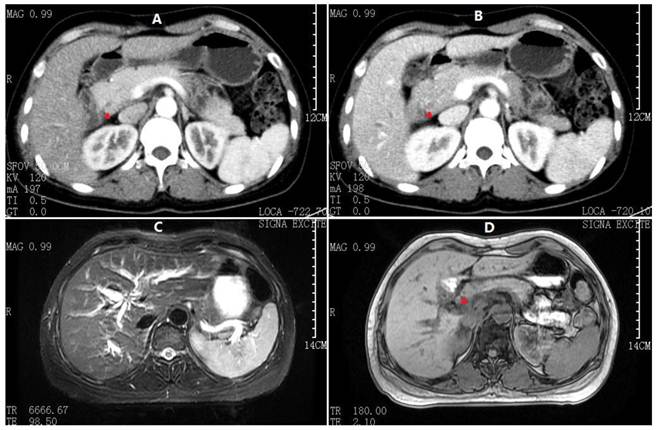

Fig 2

ERCP and postoperative T-tube cholangiography. A) ERCP showing an irregular CBD stricture (red arrowheads) with dilated intrahepatic biliary trees (green arrowheads). B) Intrahepatic bile duct dilatation resumed, but no definite bile duct stricture was observed.

On physical examination, she was a well-developed woman with a body weight of 54 kg (body mass index: 20.6 kg/m2), although she had lost 10 kg over the last 4 months. Her vital signs were stable and within normal limits, and no positive physical exam findings except scleral icterus were present. Her complete blood count, coagulation factors, erythrocyte sedimentation rate, serum immunoglobulin, CEA, AFP and CA125 were normal, whereas anti-hepatitis viruses (A-E), anti-HIV and abnormal autoimmune antibodies were negative. Urine and stool tests were consistent with obstructive jaundice. The liver function tests and CA19-9 results are summarized in Table 1. Moreover, the flow cytometry lymphocyte subpopulations were normal at 49% CD3+, 21% CD4+, 23.4% CD8+, and 19.5% natural killer cells (TBNKTM, Latonia, KY). Her chest CT, gastroscopy and colonoscopy demonstrated no abnormalities, although abdominal ultrasonography revealed extra- and intrahepatic biliary dilatation. The outer CBD diameter was dilated to 16.1 mm as its maximum, but the lumen was narrowed to almost zero due to an irregular thickened wall (7.4 mm at its maximum). No findings that were consistent with bile duct calculus, liver neoplasm or cirrhosis were identified. Furthermore, an abdominal contrast-enhanced CT scan and an MRCP produced similar findings, i.e., a hilar biliary stricture with no evidence of abdominal masses or lymphadenopathy (Fig. 1). Accordingly, an ERCP was performed, which revealed an isolated irregular proximal CBD stricture with dilated intrahepatic biliary trees and no duodenal or ampullary tumors as well as negative brush cytology (Fig. 2A). After a multidisciplinary consultation with the gastroenterologists, radiologists and oncologists, a consensus diagnosis of primary sclerosing cholangitis rather than cholangiocarcinoma was made, partly due to the lack of malignant features consistent with cholangiocarcinoma in all of the medical images. Thus, the patient was transferred to the Gastroenterology Dept. and received a conventional diagnostic plan of glucocorticoid-free treatment. Unfortunately, within the first week posterior to the ERCP, her hyperbilirubinemia worsened, with TBil and DBil increasing to 203.5 μmol/L and 123.1 μmol/L, respectively. At that time, a repeat MRCP revealed a more indistinct biliary bifurcation and CHD, which was pathognomonic for malignancy (Fig. 1F). Therefore, a hepatic hilar cholangiocarcinoma (Klatskin tumor) emerged as the new presumptive diagnosis, and thus, an exploratory laparotomy was scheduled after comprehensive consent was obtained.

Next, following the operation, the blood, bile, sputum, CSF, urine and stool samples were cultured simultaneously with ink staining at least in triplicate. All samples were negative for Cryptococcus, but the final paraffin pathology of the intraoperative biliary samples confirmed the definite diagnosis. Microscopic examination demonstrated numerous encapsulated yeast-like organisms measuring 7-10 μm in diameter scattered in multinucleated giant cells and fibrous tissues throughout the CBD and gallbladder wall. The periodic acid methenamine silver stain, periodic acid Schiff stain and India ink stain were all positive (Fig. 4), whereas the pathogen identified by polymerase chain reaction from the paraffin-embedded gallbladder was Cryptococcus neoformans (VNI type1) [3]. As soon as she completed an uneventful recovery, she was transferred to the Gastroenterology Dept. again for anti-fungal therapy (beginning on POD11), an itraconazole regimen consisting of 2 weeks of inpatient intravenous injections (Sporanox® IV, Xian-Janssen Pharmaceutical Ltd., Beijing, China) followed by 10 weeks of per os outpatient therapy (Sporanox® Capsule). At two weeks after discharge (i.e., 4 weeks after starting the therapy), her transaminases had returned to normal levels, whereas TBil/DBil levels normalized after an additional 4 weeks. Moreover, her T-tube was removed after a cholangiography (Fig. 2B).